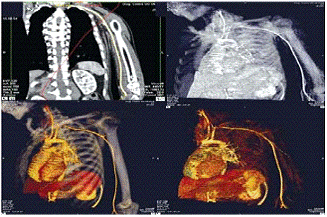

Рисунок 4.1 - КТ-ангиография сосудов головного мозга. Аневризма передней соединительной артерии головного мозга. На поверхности сосуда видны многочисленные бляшки.

Рисунок 4.2 - Измерение диаметра просвета пораженного отдела брюшной аорты.

Затем, в галерее станции «VITREA-2» выбираем протокол 3D Vascular Color и открываются 4 окна, 3 из них в МПР проекциях, а именно, в аксиальной, фронтальной и сагиттальной и одно окно в режиме виртуального просмотра Fly Through.

Использовался метод трехмерного объемного представления (3D volume rendering); метод отображения затемненной поверхности (surface shaded display); метод максимально интенсивной проекции (МIР); метод минимально интенсивной проекции (Мin IР). Основной акцент сделан на наиболее современном методе - трехмерного объемного представления (volume rendering).

Виртуальная КТ-ангиография позволяет обнаружить потенциальные причины острой ишемии, такие как артериальный стеноз высокой степени, изъязвление бляшки или аневризму с частичным тромбированием, что позволяет предпринять тромболитическую терапию или отказаться от тромболитической терапии (рис.18-20).

Рисунок 4.3 - КТ-ангиография верхних конечностей